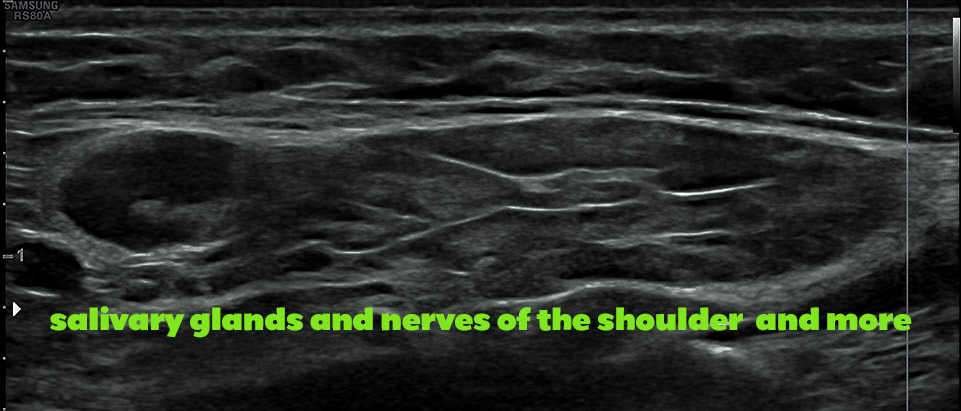

salivary glands – nerve innervation of the shoulder and other regions

14.30 – 15.10 nerve innervation of the shoulder and other regions – C MARX

14.10 – 15.50 salivary glands – A STÄRKLE-BÄR